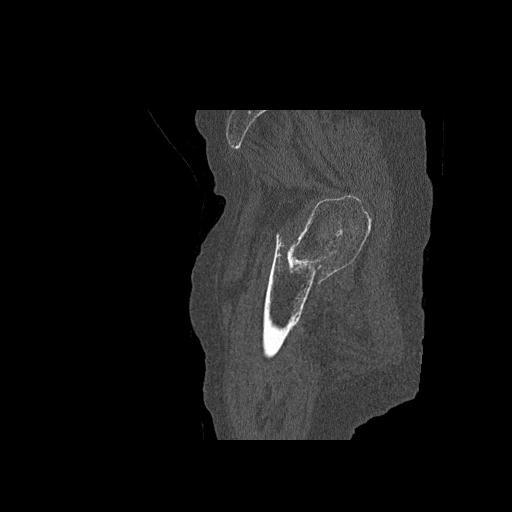

110286 2/17 股関節 2R 74歳女性 右人工骨頭